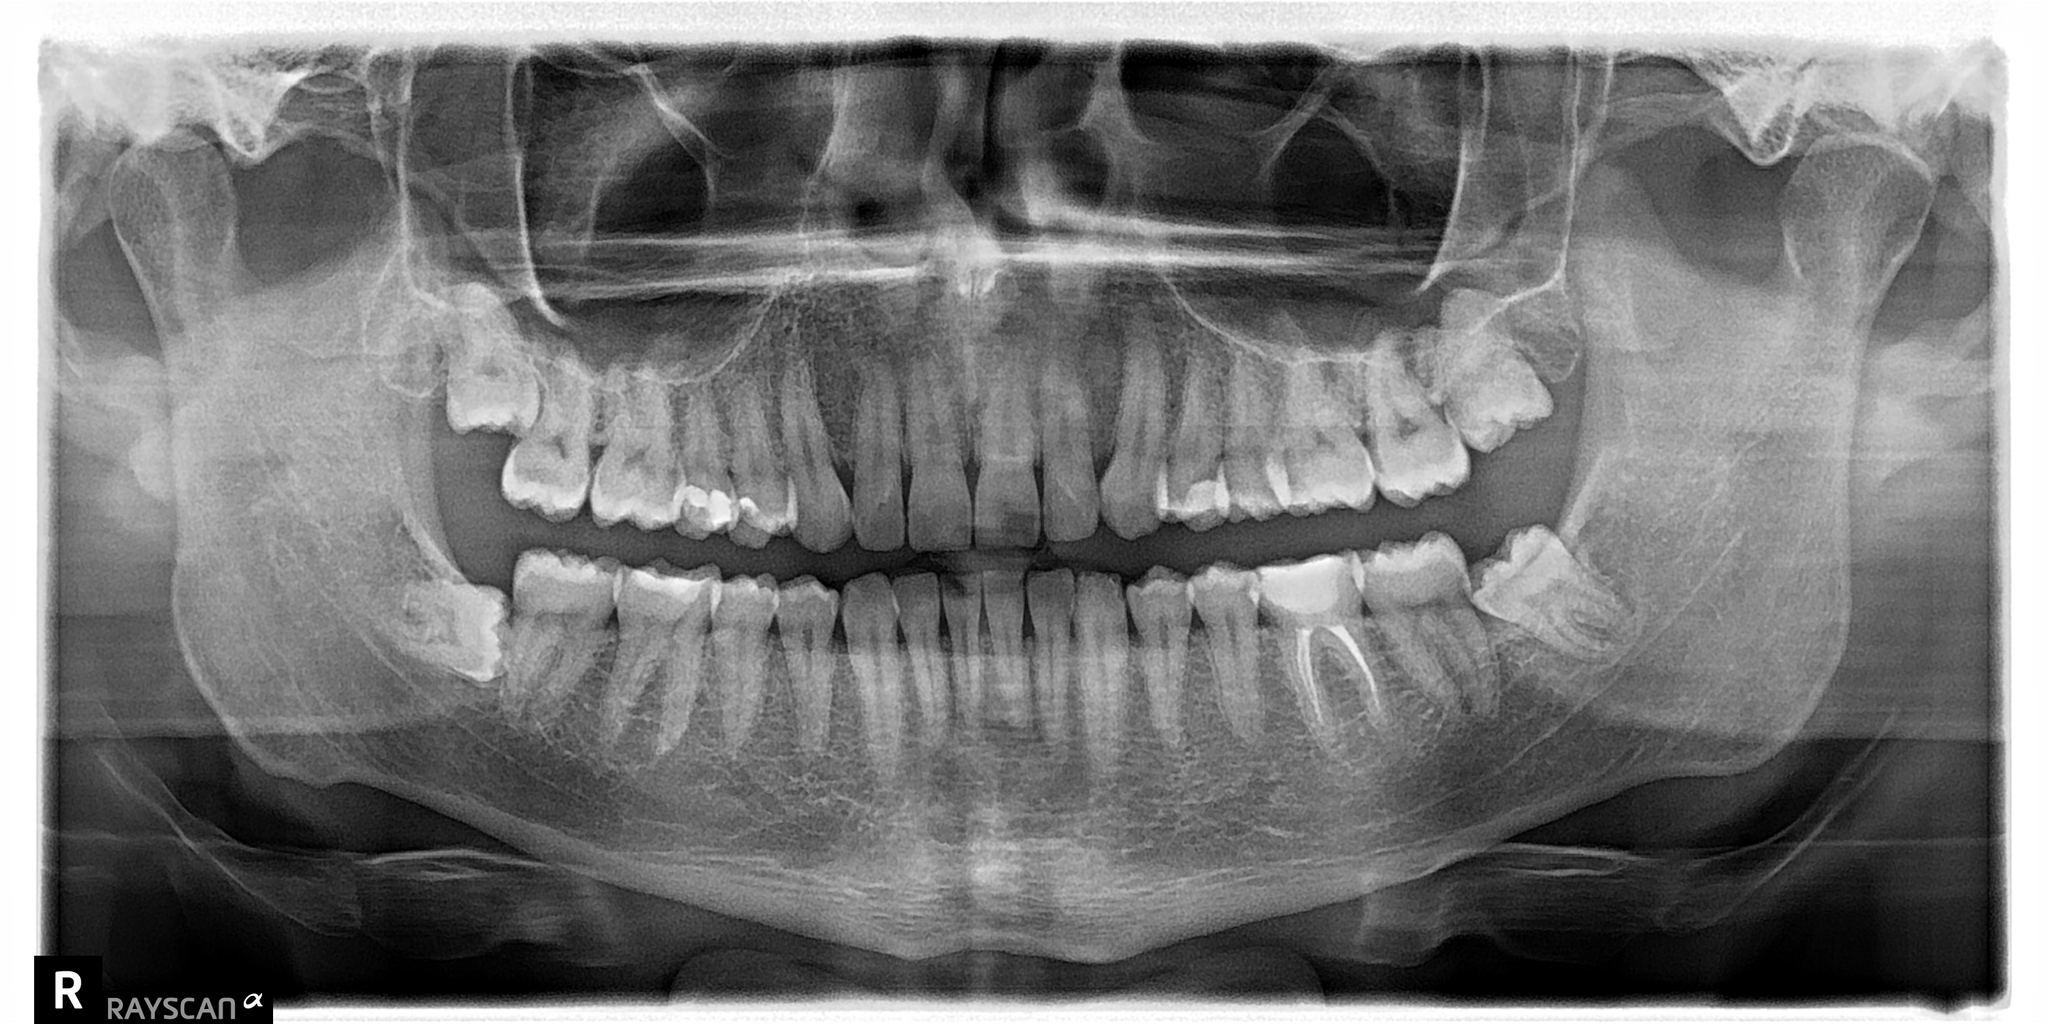

Так вот в один из таких погожих деньков в клинику обратился пациент с жалобой на дискомфорт на нижней челюсти. Ну, видать, зуб мудрости дал о себе знать, думаю я, дело то житейское. Направил на компьютерную томографию, а сам пошел попить чайку с мыслями о том, что без труда, не заморачиваясь, удалю зуб и дело с концом. Размешиваю, значит, сахарок, делаю глоток… Хорошо, думаю, сейчас бы выходной, да на фазенде, а не вот это вот все… Через несколько минут приходит ассистентка с растерянным выражением лица. Ну что, вопрошаю я, пойдем быстренько зуб удалим? Поставил стакан с чаем на стол, уверенный, что успею вернуться до того, как он остынет. Итак, мы с ассистенткой и ее недвусмысленной улыбой пошли в рентгеновский кабинет. И вот, что я увидел на компьютерной томографии:

«Сссука», – мимолетно проскользнуло у меня в голове. Так вот почему лицо ассистентки было таким. В голове крутились мысли: «ведь эта штука росла годами, а раз пациент не обращался к стоматологу, значит, не беспокоила». Вот вам, думаю я, и «не пойду к врачу, пока не заболит».

На нижней челюсти слева у пациента была внушительных размеров фолликулярная киста, которая занимала половину ветви челюсти.

Красным пунктиром я выделил границы этой кисты на срезах компьютерной томографии. Зуб, как вы можете заметить, находится аж у угла челюсти. Если говорить простым языком, то зуб сместился ввиду давления, которое формируется внутри кисты, за счёт чего, кстати, она и увеличивается. Киста достаточно большая, в связи с чем корни 6-го и 7-го зуба были вовлечены в воспалительный процесс. Если сравнить расположение 8-ки с противоположной стороны, то можно заметить, что она располагается намного ближе к 7-му зубу.